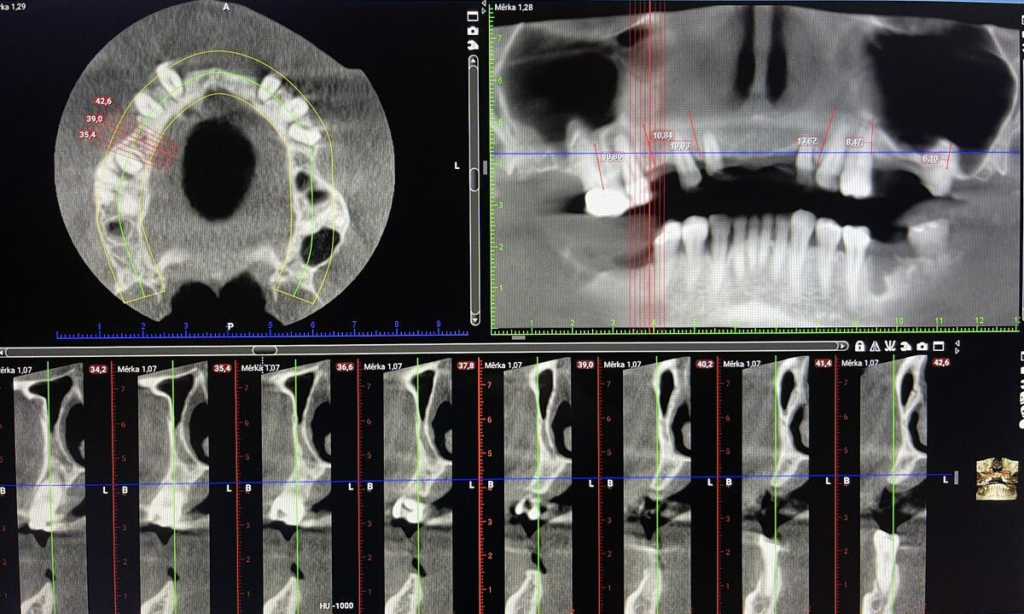

- CBCT 3D snímkování, intraorální skener

- CBCT 3D, vyšetření, fotodokumentace

- volba typu implantátů a finální práce

Technika All-on-X — I. fáze